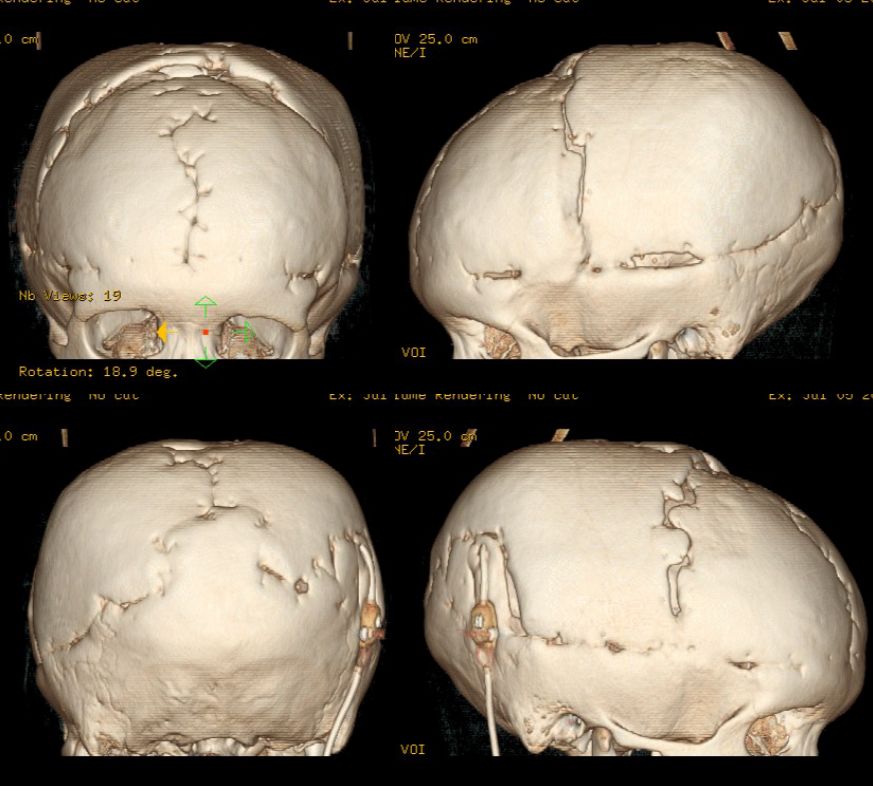

缩颅术后7年随访复查,显示外观基本正常,颅骨三维重建愈合良好(图8)。

![]()

图8. 术后7年随访,外观基本正常,头颅三维CT显示颅骨愈合良好。